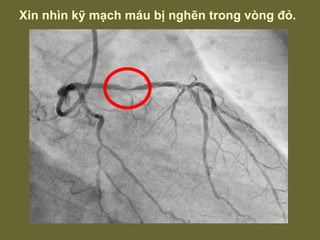

Xin nhìn kỹ mạch máu bị nghẽn trong vòng đỏ.

Xin nhìn kỹmạch máu bị nghẽn trong vòng đỏ.